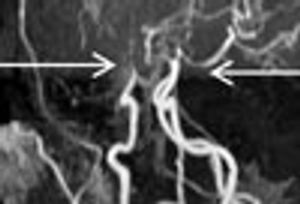

Sixteen-year-old African American boy with progressive loss of vision in the left eye over 2 weeks. He also had pain around the left orbit with some radiation to the temple. His mother reported that one side of his face appeared to be more flushed when he exerted himself; he had not seen a physician for this problem. He had no seizures or hemiparesis and was cognitively intact.